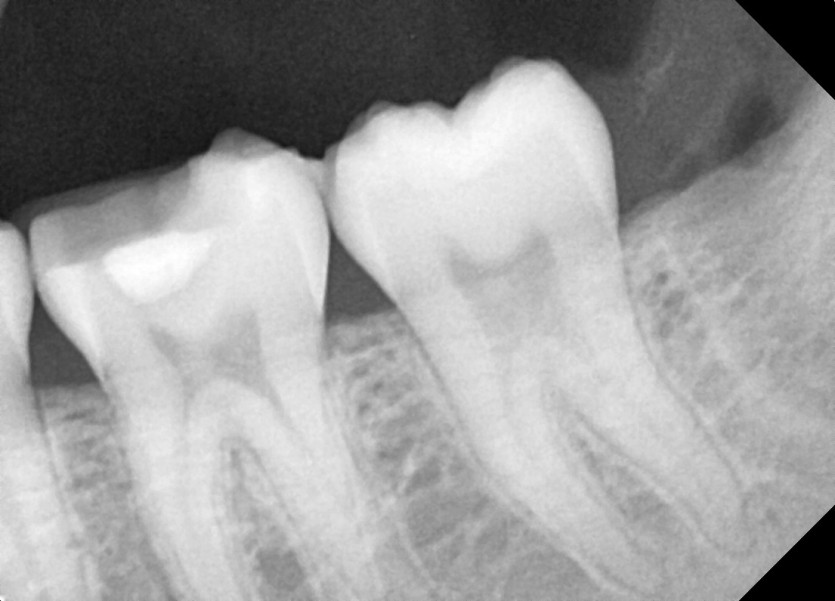

#18,28,38,48 사랑니 발치

구강 외과 전문의가 당일 발치했습니다.